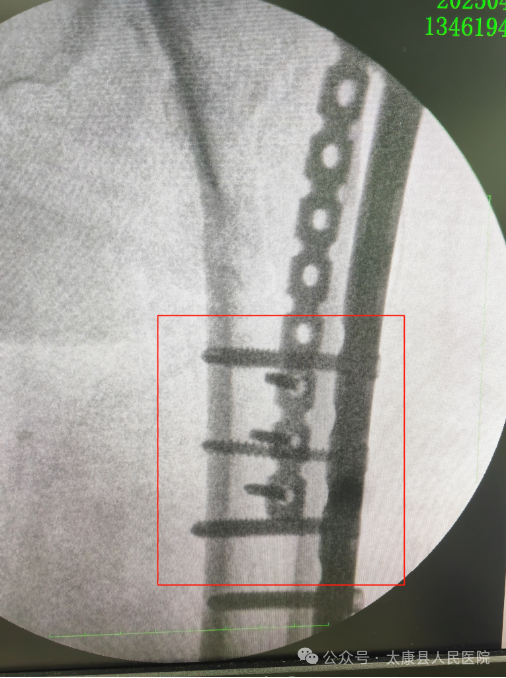

一场多学科联合救治战役迅速打响:麻醉科量身定制精准麻醉套餐 ;心内科24小时动态监测心肺功能; ICU提前介入制定术后管理方案。经过48小时紧锣密鼓的术前准备,在王保华主任医师的主刀下,手术团队凭借毫米级精准操作,仅用100毫升出血量完成骨折复位内固定,最大程度减少组织损伤。